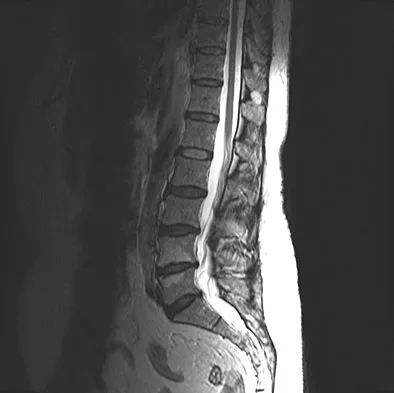

An 81-year-old man with severe low back pain reports right extensor hallucis longus and anterior tibialis weakness and difficulty urinating over the past 24 hours. He has a temperature of 101 degrees F (38.3 degrees C). MRI scans are shown in Figures 31a and 31b. Management should consist of

A 50-year-old man with no history of trauma reports new-onset back pain after doing some yard work the previous day. He reports pain radiating down his leg posteriorly and into the first dorsal web space of his foot. MRI scans are shown in Figures 3a through 3c. What nerve root is affected?